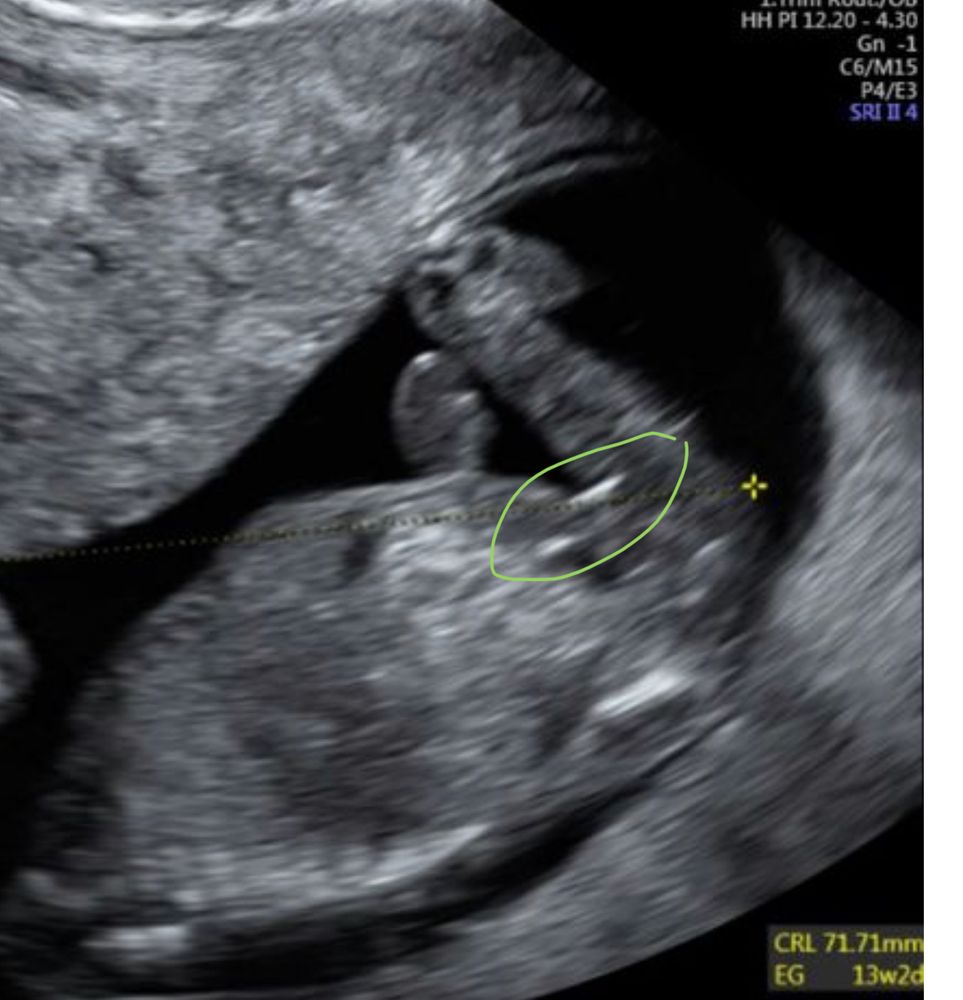

я сейчас о горизонтальной белой полосочке справа?

или мне кажется и на 13 неделе ещё толком ничего не ясно

На девочку похоже. У нас также было. Я сразу девочку увидела, а врач не стала предполагать. В итоге девочка и родилась.